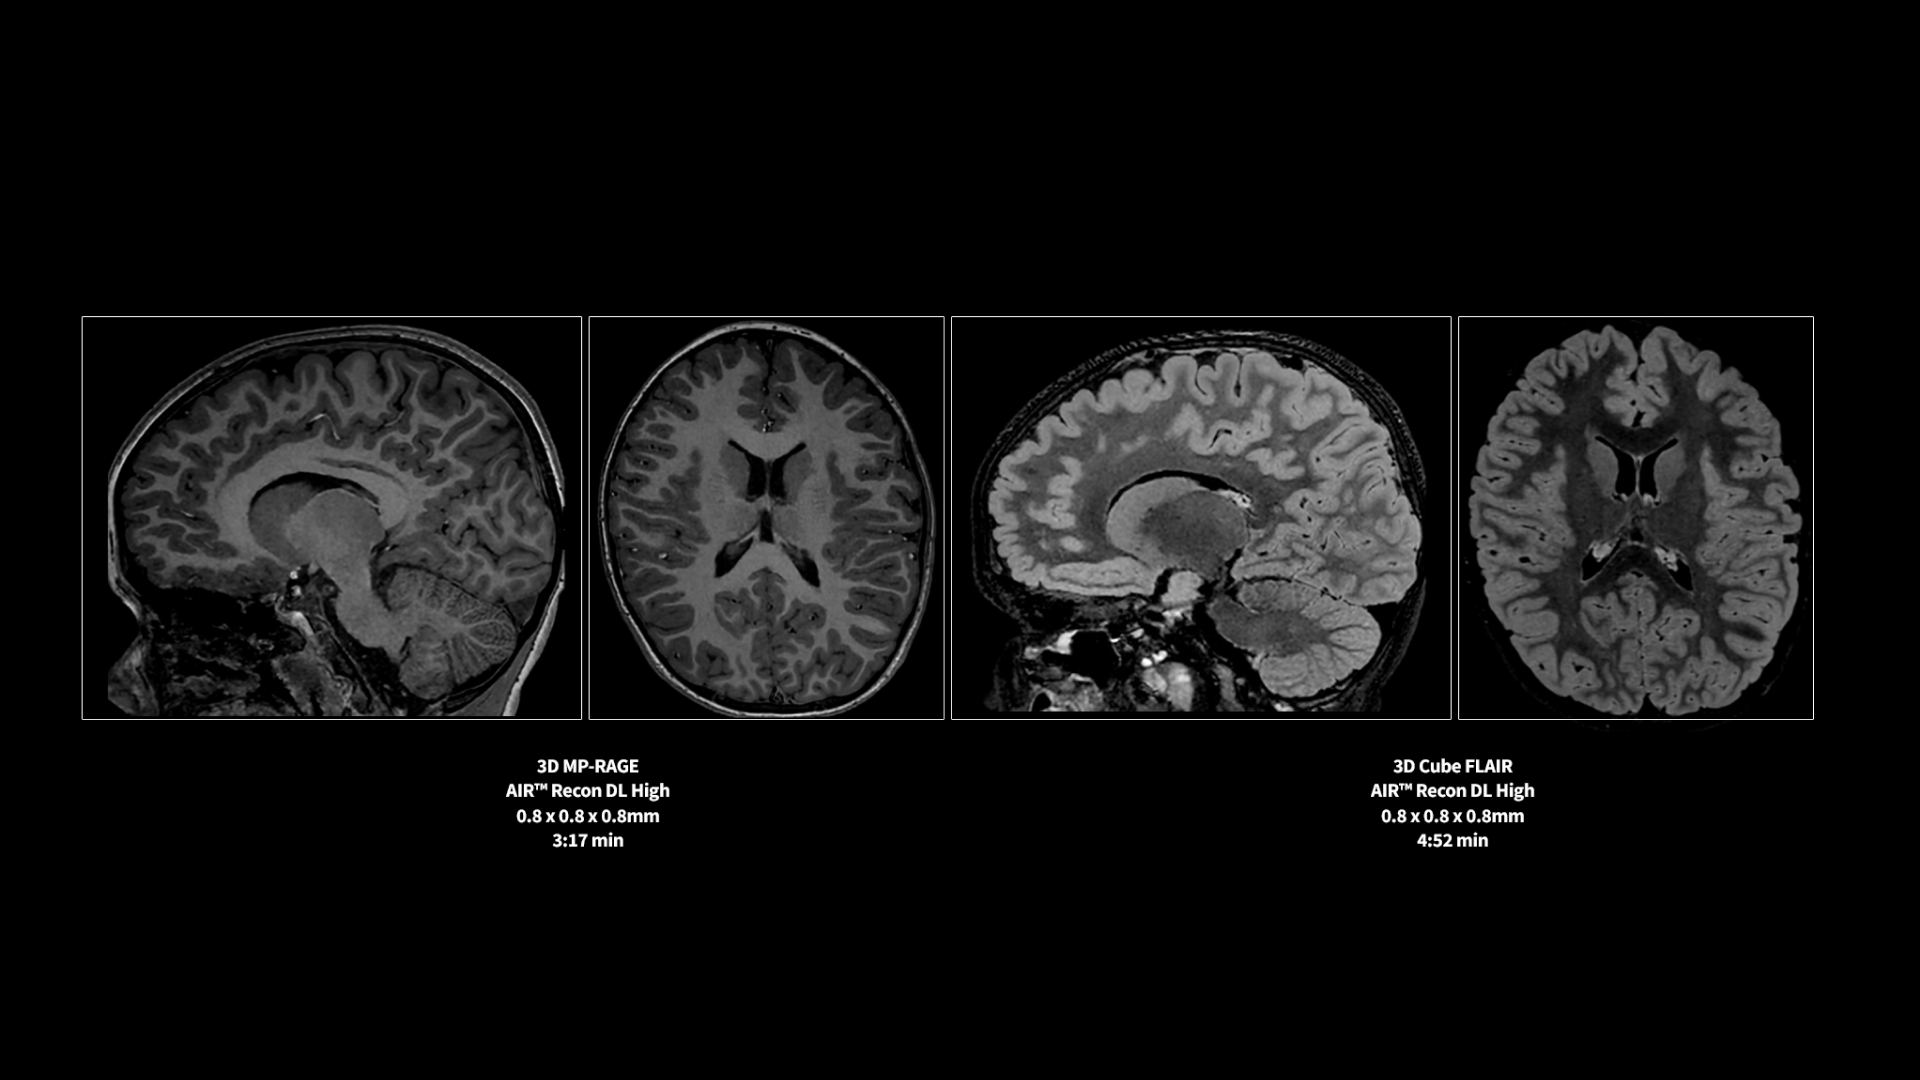

Clinical confidence

Revolutionary, deep-learning-based reconstruction techniques such as AIR™ Recon DL provide sharper, clearer, and accurate images